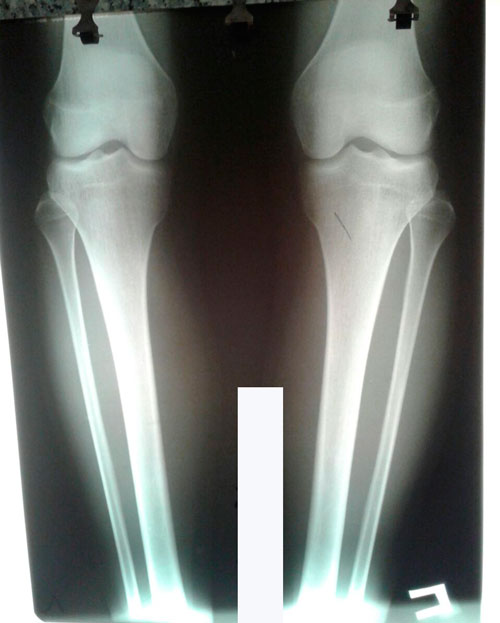

Исходник - 17 лет.

Дата операции 30.05.2017г.

Имеется Ротация.

Дата снятия аппаратов 10.08.2017г.

Срок лечения 70 дней.